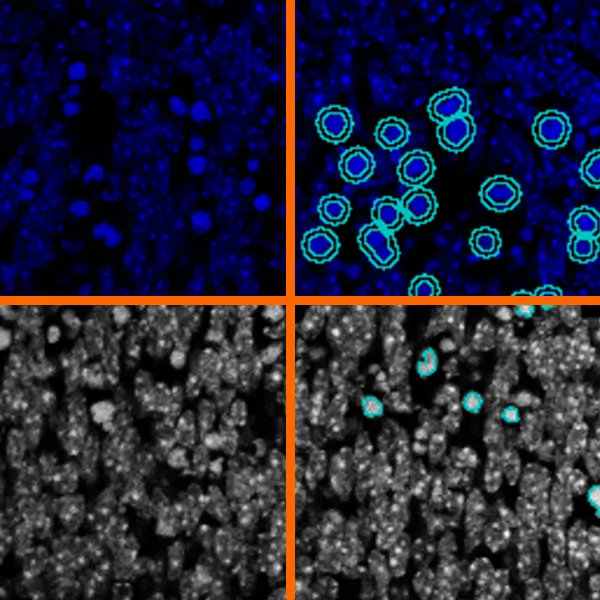

Applications of AI in Cell Segmentation

Accurate cell segmentation is the foundation of tissue cytometry. AI-powered methods, such as deep learning, improve accuracy, reduce errors, and streamline workflows. TissueGnostics integrates AI-based segmentation with phenotyping, spatial analysis, and dot detection.